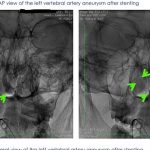

Magnetic resonance imaging showed a cerebral aneurysm of the left vertebral artery about to rupture.

Emergency minimally invasive catheter needle insertion surgery, 1 hour internal vascular treatment, implantation of blood bypass stents to divert blood into fragile cerebral aneurysms, prevent aneurysm rupture and repair blood vessels